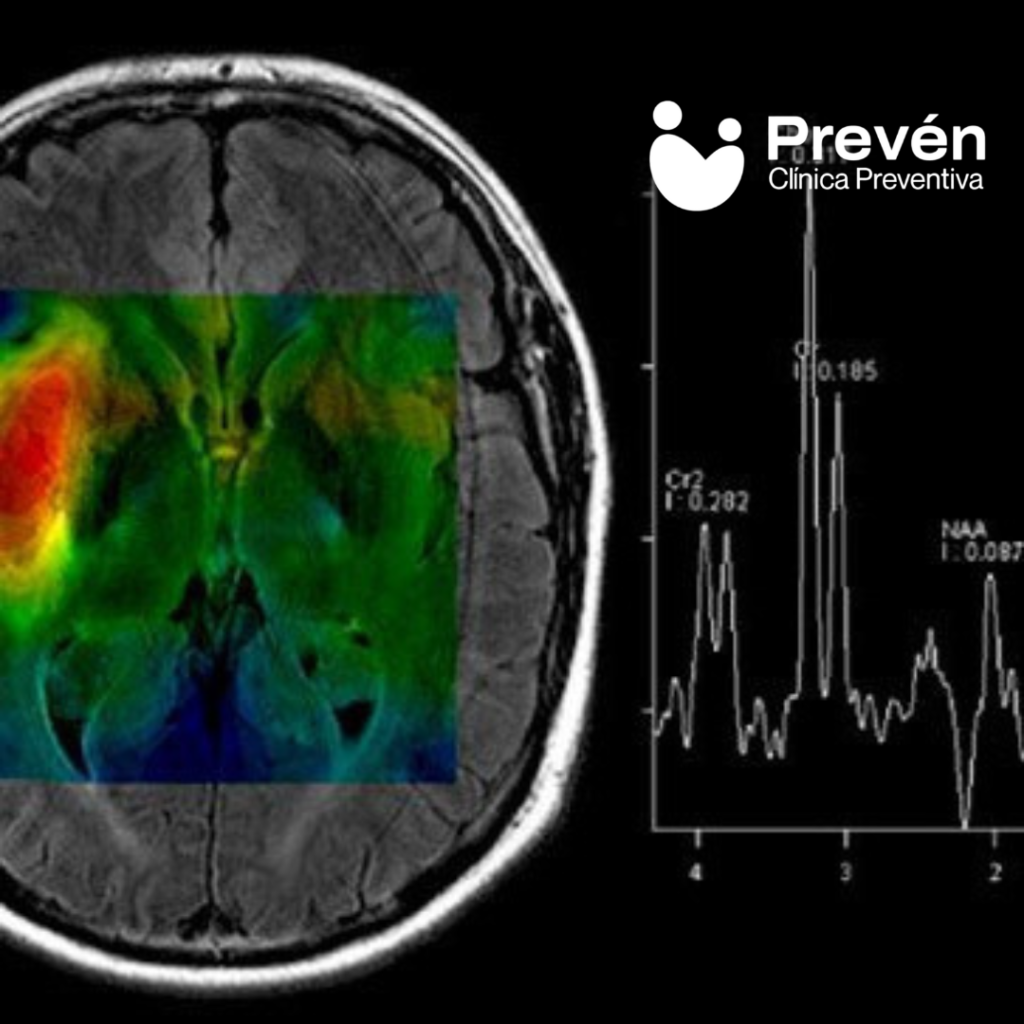

ESPECTROSCOPIA CEREBRAL

• Espectroscopia Cerebral

La RMN (en inglés, MRI) usa campos magnéticos y radiofrecuencia para generar imágenes detalladas de órganos y tejidos. No emplea rayos X. En medicina, combinamos secuencias como T1/T2, difusión (DWI/ADC), STIR y, cuando es útil, perfusión dinámica (DCE) con gadolinio.

Así localizamos lesiones, diferenciamos tejidos y apoyamos decisiones como biopsias dirigidas, estadiaje o vigilancia. Nuestro protocolo en 1.5T optimizado con AIR Recon DL mejora señal y reduce ruido para obtención más rápida y cómoda.

• Secuencias: T1/T2, STIR (edema), DWI/ADC (difusión), DCE (perfusión).